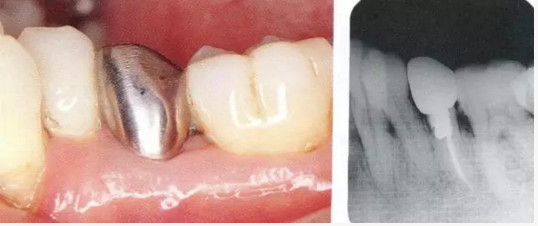

2222.png

▲圖18-1,2

▲圖18-1  左下5佩戴金屬冠,但是由于近遠中接觸點的位置和大小不合適,導(dǎo)致鼓形間隙基本消失。

▲圖18-2  同部位的X光片??梢钥吹烬l下有牙結(jié)石沉積,并且有牙槽骨吸收現(xiàn)象。